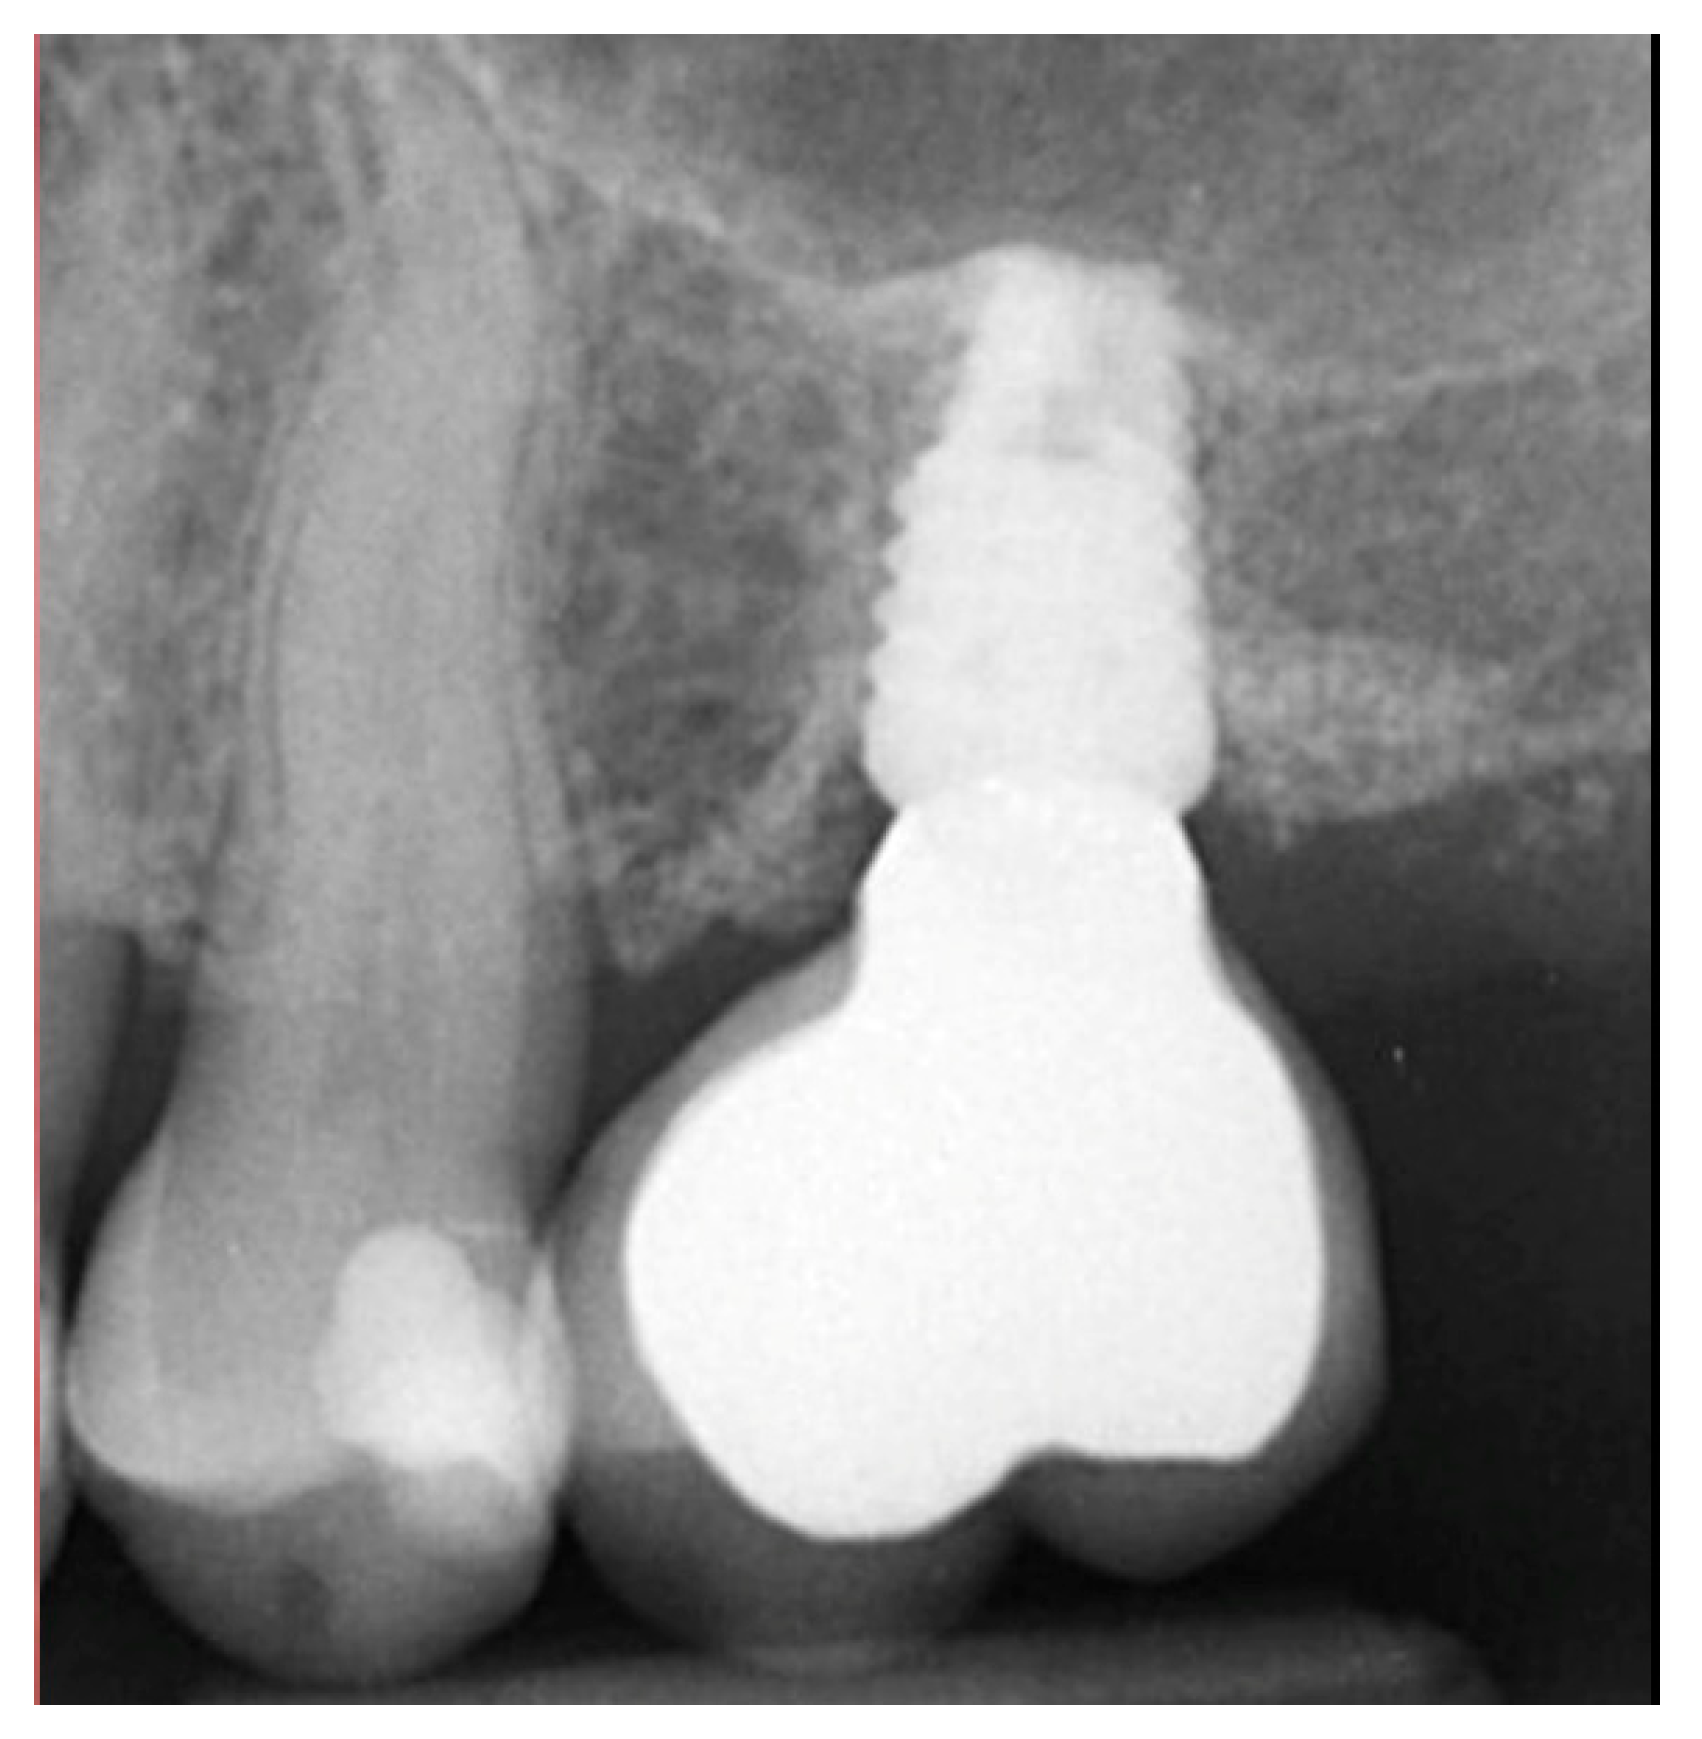

Figure 6.

Exposure of the integrated implant after 10 weeks of healing (left). Screw-retained restoration placement (middle) and a radiograph to document seating of the restoration at the implant connector demonstrating conversion of the graft material to host bone (right).

A radiograph obtained at the 2-year recall demonstrated stability of the graft surrounding the implant (Figure 7). The implant and restoration remain in function with no issues reported by the patient or noted at routine recall appointments during the prior period since completion of the restoration.

Figure 7.

Radiograph at 2 years post-restoration placement demonstrating stability and maintenance of the grafted area.